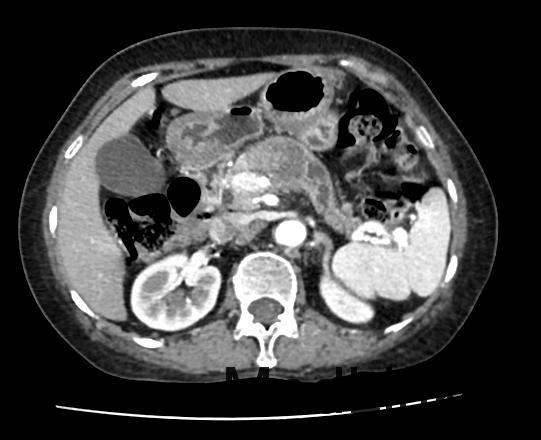

患者女,72岁,主因“消瘦半年,查体发现胰腺肿物1月”入院;患者半年前开始无明显诱因出现消瘦,体重逐渐减轻,约有3Kg。肿瘤标志物检查:癌胚抗原和CA-199增高。腹部CT平扫和腹部CT增强检查示:胰腺颈部肿瘤性病变,考虑胰腺癌可能性大。现为进一步诊治收入我科。

查体:无异常。 辅助检查:肿瘤标志物;癌胚抗原7.82ng/ml↑,CA-199197,60U/ml↑。 腹盆CT平扫;1、胰腺颈部不规则低密度影,占位性病变待除外,建议增强CT检查。 腹部CT增强;1、胰腺颈部肿瘤性病变,考虑胰腺癌可能性大,建议进一步检查。

诊断:1.胰腺肿物 胰腺癌 治疗:腹腔镜探查、转开腹胰体尾+脾切除术(术中冰冻病理提示胰腺癌)